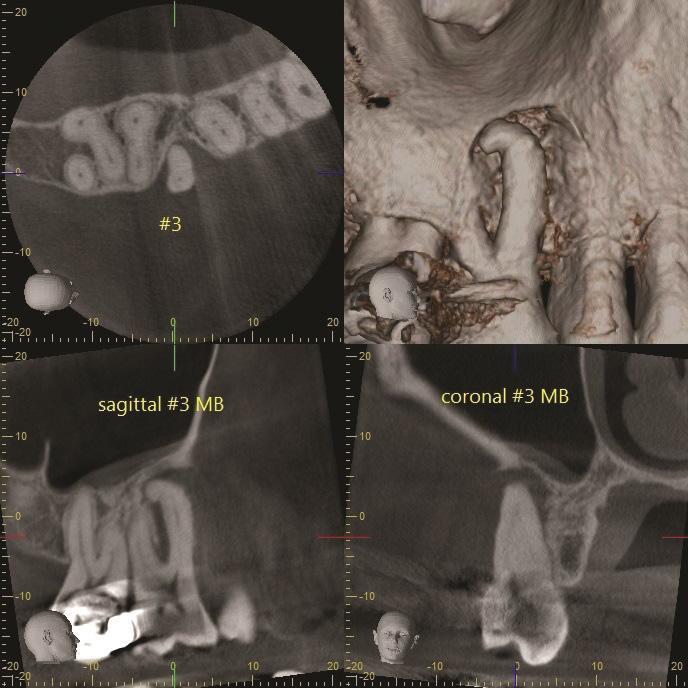

Фото 4: 3D-изображение КЛКТ зуба 1.6, демонстрирующее апико-маргинальный дефект кости, затрагивающий мезиально-щечный корень при стабильных сросшихся дистально-щечном и небном корнях.